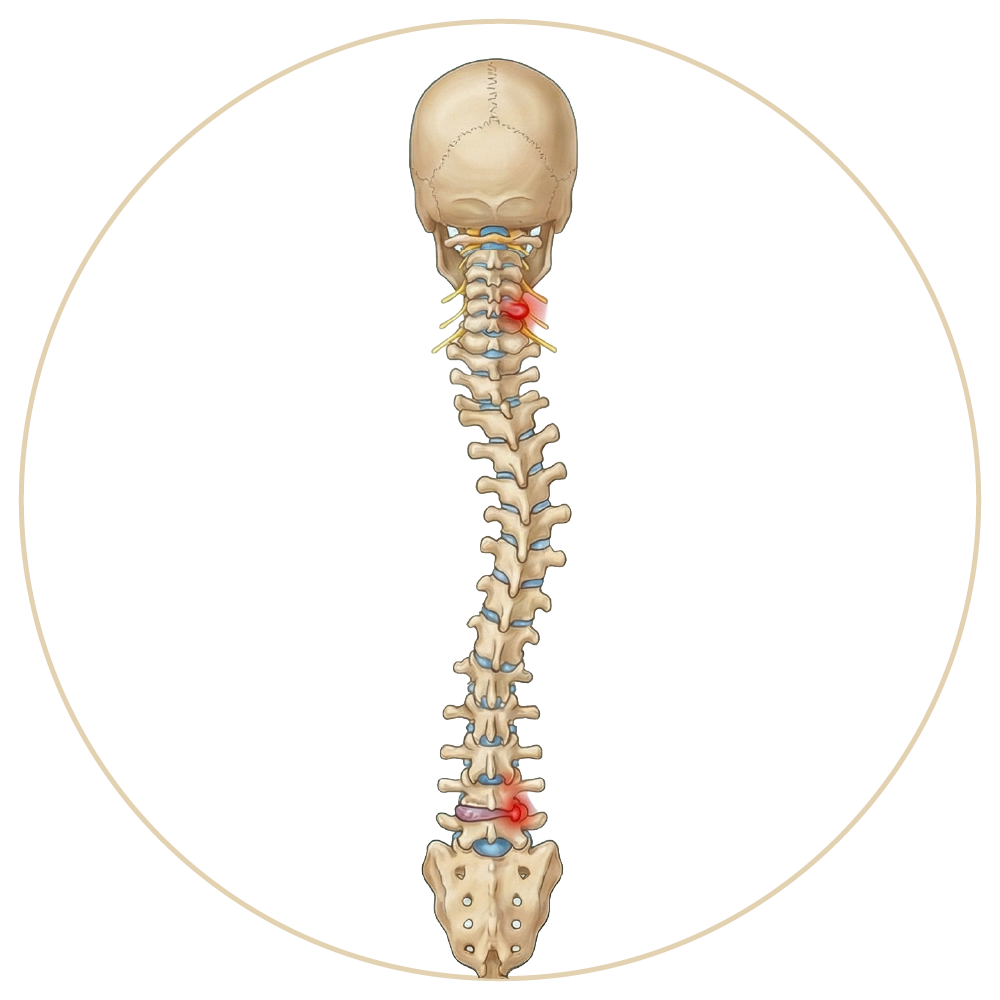

OmurgaHastalıkları

Skolyoz

Omurga Hastalıkları ve Tedavileri

Omurga (Bel - Boyun - Sırt) Hastalıkları